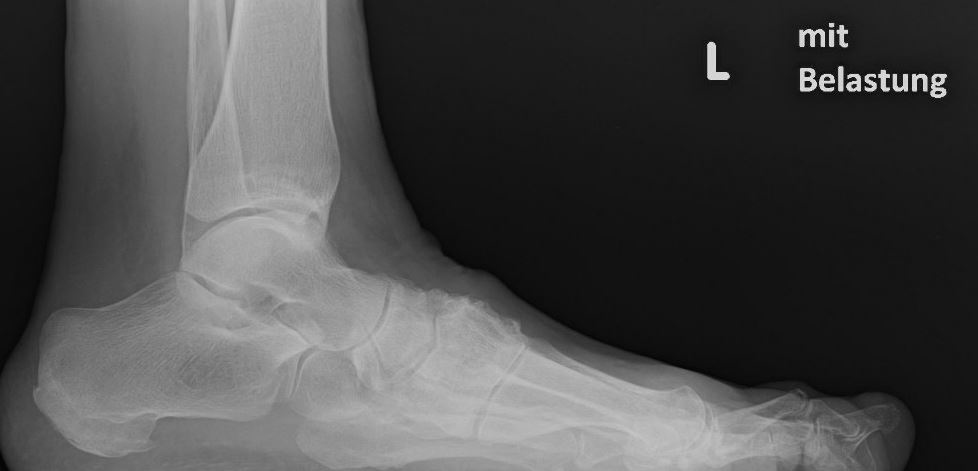

Eine Röntgenaufnahme unter Belastung mit Abbildungen des ganzen Fußes a. p. (mit 15-20° Röhrenkippung) und seitlich, sowie Schrägaufnahmen, reichen meist zur Diagnose. Manchmal ist ein MRT und DVT ergänzend hilfreich. Selten wird die Indikation für ein SPECT CT gestellt (Abb. 6).

Zum Lesen der Bildbeschreibung und zur Vollansicht bitte das Bild anklicken. Bild: C. Hase.

• konventionelle Röntgenbilder mit Belastung im Stehen a. p. und seitlich, ggf. schräg (Abb. 9, 10 und 11).